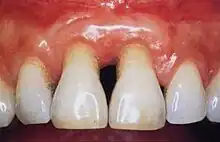

Healthy gingiva can be described as stippled, pale or coral pink in Caucasian people, with various degrees of pigmentation in other races. The gingival margin is located at the cemento-enamel junction without the presence of pathology. The gingival pocket between the tooth and the gingival should be no deeper than 1–3mm to be considered healthy. There is also the absence of bleeding on gentle probing.[11]

Signs and symptoms of periodontal disease: bleeding gums, gingival recession, halitosis (bad breath), mobile teeth, ill-fitting dentures and buildup of plaque and calculus.[16]

An individual's host response plays an important role in the pathogenesis of periodontal disease. Even in a mouth where the gingiva appear healthy, there is constant low-level inflammatory response facilitated by the host to manage the constant bacterial load of plaque micro-organisms. Leukocytes and neutrophils are the main cells that phagocytose bacteria found in the gingival crevice or pocket. They migrate from the tissues in a specialized exudate called gingival crevicular fluid also known as GCF. Neutrophils are recruited to the gingival crevice area as they are signalled to by molecules released by plaque microorganisms. Damage to epithelial cells releases cytokines which attract leukocytes to assist with the inflammatory response. The balance between normal cell responses and the beginning of gingival disease is when there is too much plaque bacteria for the neutrophils to phagocytose and they degranulate, releasing toxic enzymes that cause tissue damage. This appears in the mouth as red, swollen and inflamed gingiva which may bleed when probed clinically or during tooth brushing. These changes are due to increased capillary permeability and an influx of inflammatory cells into the gingival tissues. When gingival disease remains established and the aetiology is not removed, there is further recruitment of cells such as macrophages, which assist with the phagocytic digestion of bacteria, and lymphocytes, which begin to initiate an immune response.[22] Pro-inflammatory cytokines are produced inside the gingival tissues and further escalate inflammation, which impacts the progression of chronic systemic inflammation and disease. The result is collagen breakdown, infiltrate accumulation as well as collagen breakdown in the periodontal ligament and alveolar bone resorption. At this stage, the disease has progressed from gingivitis to periodontitis and the loss of supporting periodontium structure is irreversible.[21]

Chronic periodontitis

The inflammation of the gums and irreversible destruction of the alveolar bone and surrounding structures of the teeth, which is usually slow progressing but can have bursts. Local factors explain presence of disease, such as diet, lack of oral hygiene, plaque accumulation, smoking, etc. It is characterized by pocket formation and recession of the gingiva (shrinkage of the gums). Treatment and maintenance are important in stopping disease progression and to resolve the inflammation. Treatment usually consists of scaling and root planning, surgical therapy, and regenerative surgical therapy. After treatment, patient care and regular maintenance check-ups are important to completely eradicate the disease and present its recurrence. This is done through plaque control and removal: twice daily toothbrushing and daily interdental cleaning; chlorhexidine mouthwash can also be effective. The patient should also present to a dentist for maintenance check-ups at least every three months for an in-office check-up and if necessary, plaque control.[56]